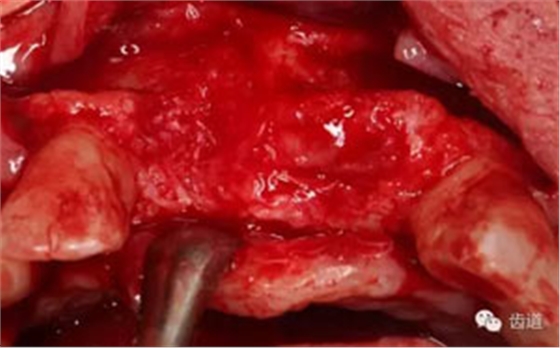

患者不愿才用自體骨移植,遂建議采用同種異體骨骨塊(皮質(zhì)骨)進(jìn)行骨環(huán)手術(shù)。 種植手術(shù):

骨環(huán)技術(shù)可以解決水平和垂直向的骨不足,但一般采用自體骨。自體骨雖然是骨移植的金標(biāo)準(zhǔn),但是需要在第二術(shù)區(qū)取骨,患者疼苦較大。同種異體骨塊來(lái)自于人類,和自體骨的結(jié)構(gòu)非常類似,成骨性能良好。故筆者選用同種異體骨塊進(jìn)行骨環(huán)手術(shù),在國(guó)內(nèi)外都是首次。該病例筆者隨訪觀察了一年,目前骨環(huán)比較穩(wěn)定。 白石 男 重慶醫(yī)科大學(xué)附屬口腔醫(yī)院種植科主治醫(yī)師,講師,碩士; 國(guó)際種植協(xié)會(huì)高級(jí)??漆t(yī)師,華西口腔醫(yī)學(xué)院碩士畢業(yè)生; 從事種植外科和種植修復(fù)臨床工作10年; 曾接受系統(tǒng)化種植培訓(xùn),有豐富口腔種植治療經(jīng)驗(yàn),擅長(zhǎng)復(fù)雜種植的設(shè)計(jì)與修復(fù),對(duì)全口種植義齒、種植美學(xué)修復(fù)技術(shù)和常規(guī)精密義齒修復(fù)有較深研究。 參加國(guó)內(nèi)外多次會(huì)議,并屢次獲得病例比賽獎(jiǎng)勵(lì)。